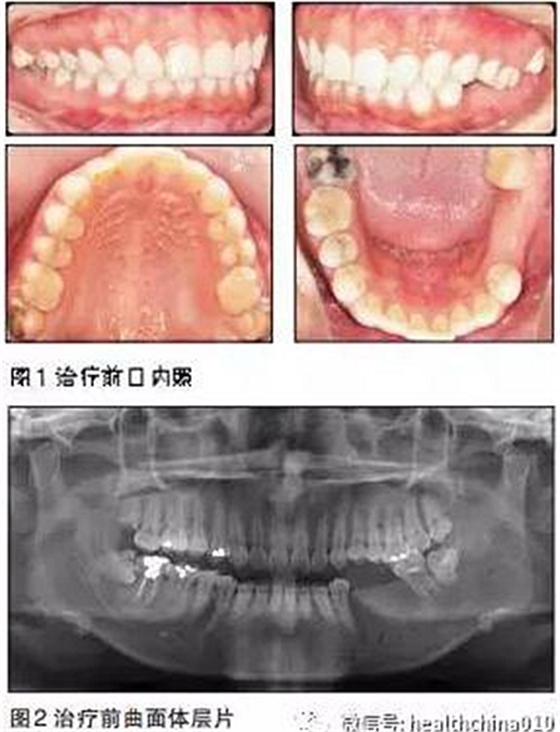

患者女性,29歲。主訴:15年前左下后牙爛牙,在當(dāng)?shù)匮揽崎T診拔除,未給予修復(fù)。

近15年來患者由于左側(cè)牙齒無法咬碎食物,一直用右側(cè)后牙咀嚼,自覺臉型逐漸不對稱,要求修復(fù)左下后牙恢復(fù)咀嚼功能。體健,無吸煙史。

患者臉型不對稱,右側(cè)大于左側(cè)。

牙周情況尚可,有少量牙結(jié)石,牙齦無明顯紅腫。35、36缺失,25、26過長,17與47,27與37正鎖牙合,咬合時(shí)26、27的牙尖頂?shù)綄︻M缺牙區(qū)牙槽嵴黏膜上。37、47死髓牙。

全口曲面體層片顯示:35、36缺失,缺牙區(qū)牙槽骨有足夠的骨高度,47未行根管治療,38、48近中阻生,18殘根,28頰面深齲近髓。